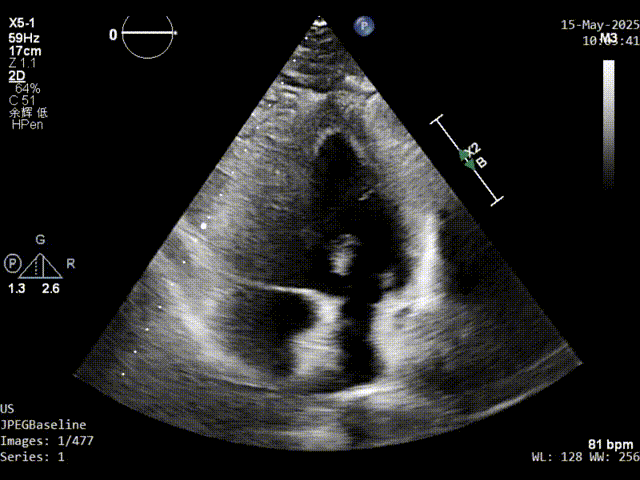

术前发泡实验超声影像

主动脉短轴切面超声影像